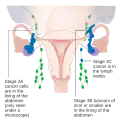

Staging

Ovarian cancer is staged using the FIGO staging system and uses information obtained after surgery, which can include a total abdominal hysterectomy via midline laparotomy, removal of (usually) both ovaries and Fallopian tubes, (usually) the omentum, pelvic (peritoneal) washings, assessment of retroperitoneal lymph nodes (including the pelvic and para-aortic lymph nodes), appendectomy in suspected mucinous tumors, and pelvic/peritoneal biopsies for cytopathology.[28][26][31][82] Around 30% of ovarian cancers that appear confined to the ovary have metastasized microscopically, which is why even stage-I cancers must be staged completely.[26] 22% of cancers presumed to be stage I are observed to have lymphatic metastases.[31] The AJCC stage is the same as the FIGO stage. The AJCC staging system describes the extent of the primary tumor (T), the absence or presence of metastasis to nearby lymph nodes (N), and the absence or presence of distant metastasis (M).[83] The most common stage at diagnosis is stage IIIc, with over 70% of diagnoses.[26]

| III | cancer found outside the pelvis or in the retroperitoneal lymph nodes, involves one or both ovaries | |||

| IIIA | metastasis in retroperitoneal lymph nodes or microscopic extrapelvic metastasis | |||

| IIIA1 | metastasis in retroperitoneal lymph nodes | |||

| IIIA1(i) | the metastasis is less than 10 mm in diameter | |||

| IIIA1(ii) | the metastasis is greater than 10 mm in diameter | |||

| IIIA2 | microscopic metastasis in the peritoneum, regardless of retroperitoneal lymph node status | |||

| IIIB | metastasis in the peritoneum less than or equal to 2 cm in diameter, regardless of retroperitoneal lymph node status; or metastasis to liver or spleen capsule | |||

| IIIC | metastasis in the peritoneum greater than 2 cm in diameter, regardless of retroperitoneal lymph node status; or metastasis to liver or spleen capsule | |||

| IV | distant metastasis (i.e. outside of the peritoneum) | |||

| IVA | pleural effusion containing cancer cells | |||

| IVB | metastasis to distant organs (including the parenchyma of the spleen or liver), or metastasis to the inguinal and extra-abdominal lymph nodes |

-

Stage 1 ovarian cancer

Stage 1 ovarian cancer -

Stage 2 ovarian cancer

Stage 2 ovarian cancer -

Stage 3 ovarian cancer

Stage 3 ovarian cancer -

Stage 4 ovarian cancer

Stage 4 ovarian cancer